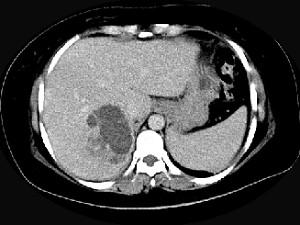

问题 女,36岁,右上腹痛,有发热,白细胞计数升高,CT检查如图,最可能诊断是 ( )

选项 A、肝黄色肉芽肿 B、肝胆管细胞癌 C、肝淋巴管瘤 D、肝脓肿 E、原发性肝癌

答案 D